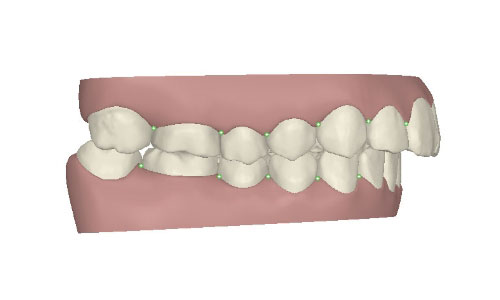

コンピューターを使って作製した透明なマウスピース型の矯正装置(アライナー)を段階的につけ替えていき、それにより歯列を矯正し、歯並びへと改善します。はじめに 治療開始から終了までのアライナーができあがってきます。マウスピース型矯正装置(インビザライン)の最大の特徴として「クリンチェック」というソフトがあります。3D のコンピュータ シュミレーション画像で、治療開始から完了までを目で見て確認することができます。

マウスピース型矯正装置(インビザライン)治療においては、クリンチェックというシミュレーションソフトを活用しております。

このクリンチェックの魅力は、治療前の現在の歯並びから治療後の歯並びを視覚化して患者様にご説明できる点にあります。

また、抜歯・非抜歯、全体矯正・部分矯正などそれぞれの治療パターンをシミュレーションすることが可能です。